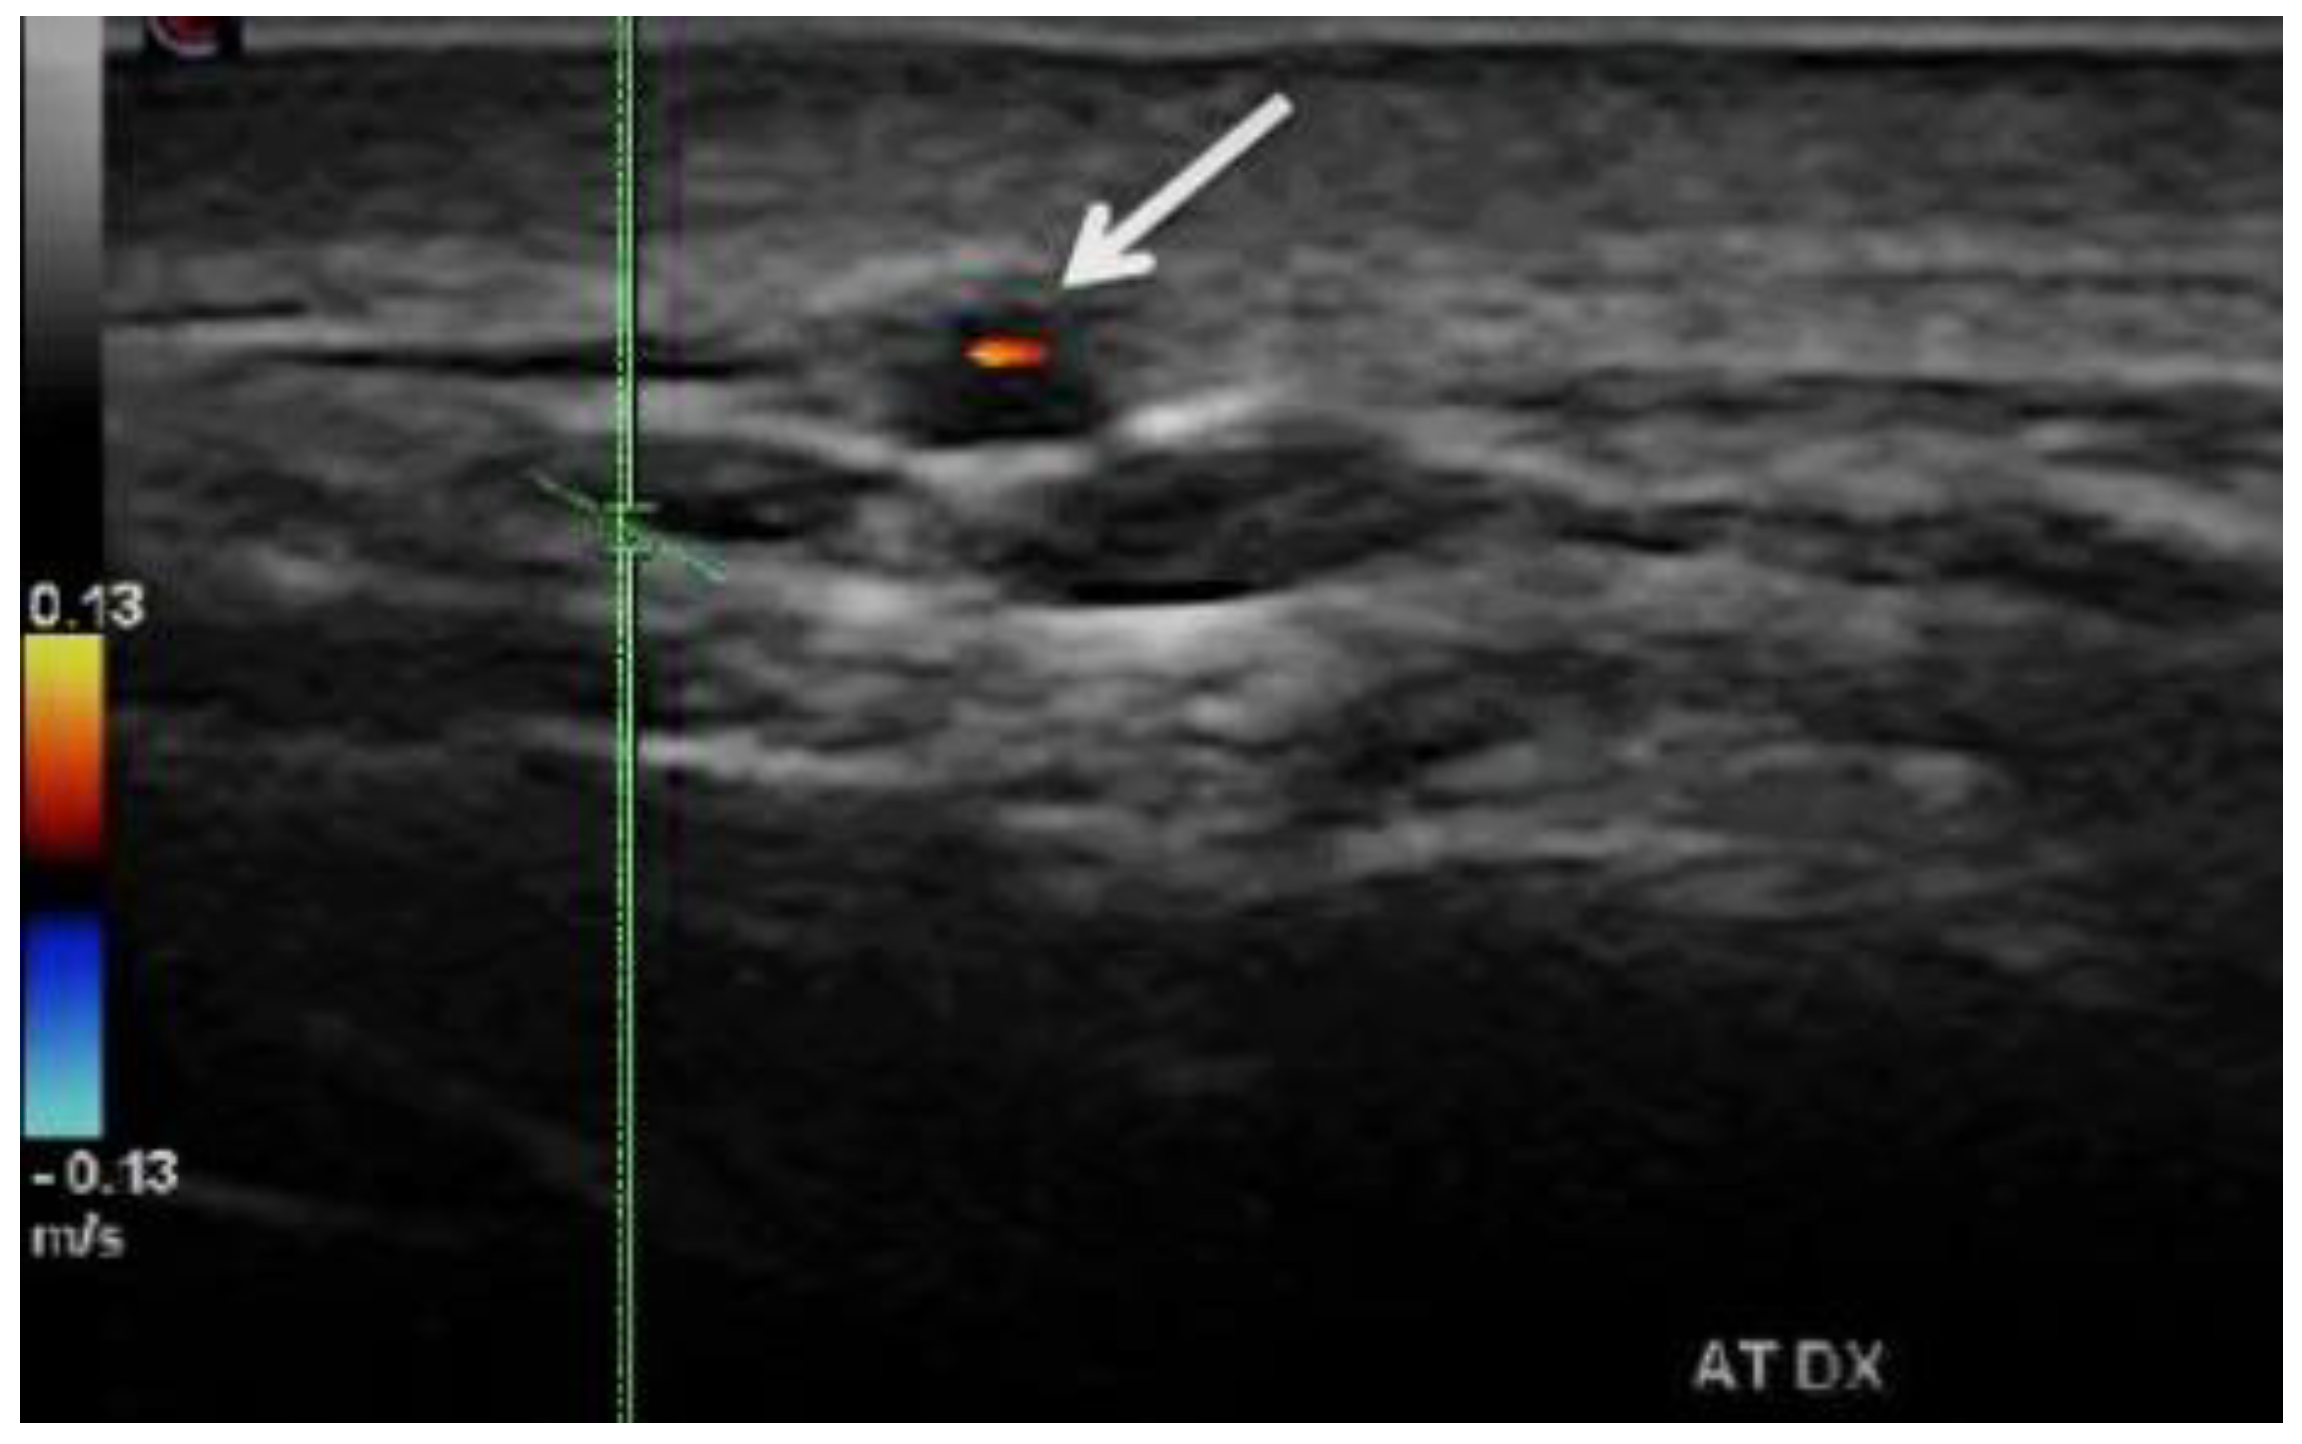

- In the acute phase of unilateral clinical eye involvement, absent (undetectable) signals in the homolateral PCAs (not corresponding to homolateral internal carotid artery occlusive disease) are classified as Doppler US features in acute arteritic AION (consecutive to GCA). In addition, we can identify a high resistance index (RI), with decreased velocities (especially EDV) in all retrobulbar vessels, in both orbits [9,10,11,12,13,14,15,60,61,62] (Table 2) [13].

- GCA acute cases with no evident clinical ocular involvement present a decrease in arterial flow in bilateral orbits, with increased RI, and diminished velocities (especially EDV). The severely diminished flow in the PCA, associated with diminished flow in the CRA and very high flow in the OA (all on the affected side) are the common US features in this type of patient. This US aspect is an essential predictor of an imminent A-AION and needs prompt treatment with high-dose corticosteroids [9,10,11,12,13,14,15,60,61,62] (Figure 7) [11].